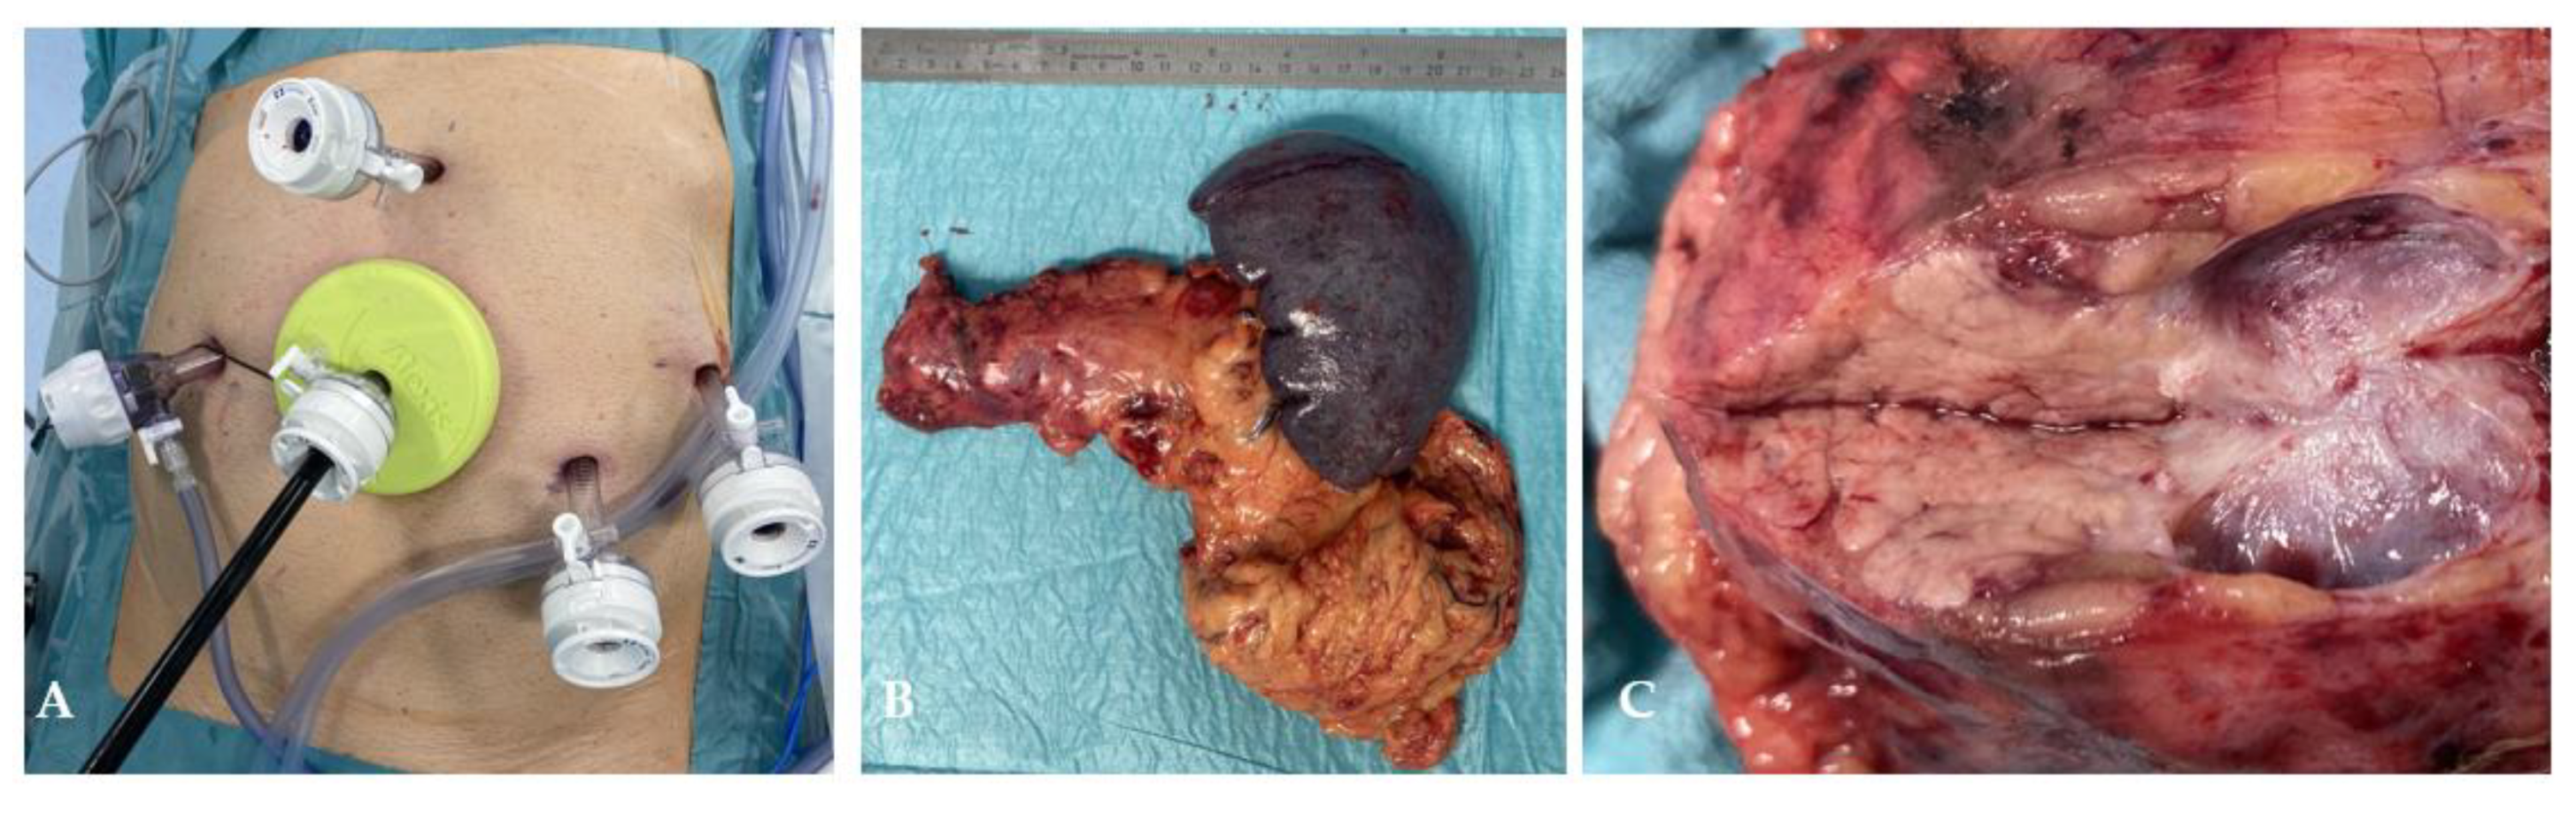

During step 2 the splenic vessels were dissected free under the pancreas, then the splenic artery divided using an Endo GIA Ultra 30 mm white cartridge, the splenic vein divided in the same manner preserving the left gastric and inferior mesenteric veins. The pancreas was divided at the level of its isthmus using a purple cartridge Endo GIA Ultra 60 mm after compressing it for 3 minutes. The pancreatic stump was temporarily covered with a small Tabotamp fleece and a gauze. After that, the pancreatic tail with the spleen was dissected free off the retroperitoneum (suppl. Video 1). Robotic arms were undocked, the supraumbilical incision was increased to 5 cm and a small Alexis wound retractor with a cap inserted. The specimen was retrieved in an Endo Bag through the Alexis retractor (Figure 5). It was then covered again for laparoscopic control of the pancreatic stump, covering it with a Tachsoil fleece, irrigation and drain placement.

Figure 5. View of ports and wound retractor during specimen extraction (A); specimen consisting of pancreatic tail, spleen and omentum (B); cut surface of the cystic lesion (C).